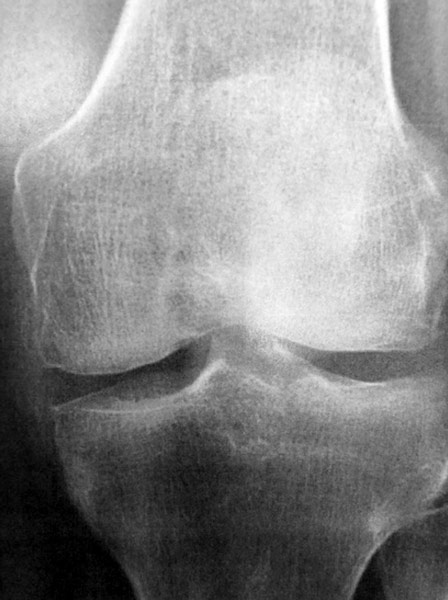

Arthrose interne isolée (pincement à la radio), Homme, 60 ans.

Arthrose interne (pincement à la radio) associée à une nécrose du condyle fémoral interne (visible à l’IRM). Homme, 65 ans.

Arthrose externe isolée, survenue après une fracture du plateau tibial externe opérée par plaque. Homme 55 ans; douleur, raideur, boiterie.

Arthrose des trois compartiments du genou (tri-compartimentale).